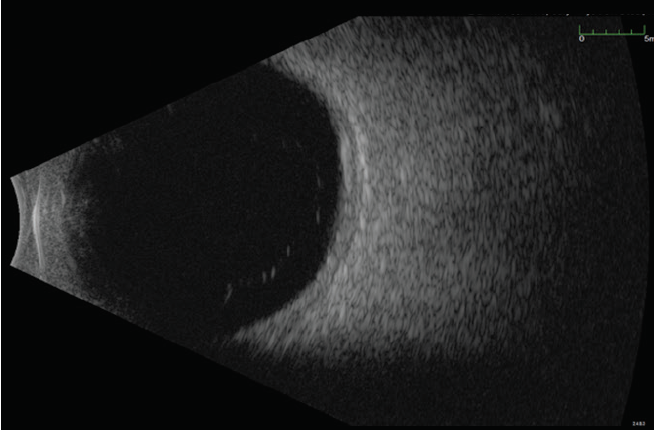

On examination, his VA was 20/70-1 OD and 20/20-1 in the left eye (OS). Anterior segment evaluation was normal. Posterior segment examination was notable for a temporal choroidal lesion OD. Fundus color photography documented an amelanotic choroidal lesion with elevation OD (Figure 1). Fluorescein angiography was initially interpreted as indicating choroidal melanoma: amelanotic pigmentation with intrinsic vascularity and hyperfluorescence with progressive leakage (Figure 2). B-scan ultrasound confirmed significant elevation of the retina and a large area of choroidal excavation measuring 15 mm by 16 mm by 6.7 mm (Figure 3).

<p>Figure 3. Ocular ultrasound shows an elevated mass, 15 mm by 16 mm by 6.7 mm.</p>

Figure 3. Ocular ultrasound shows an elevated mass, 15 mm by 16 mm by 6.7 mm.